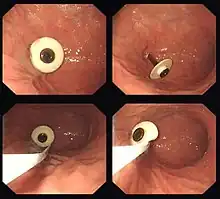

Retrait d'un corps étranger planté dans la paroi de l'estomac.